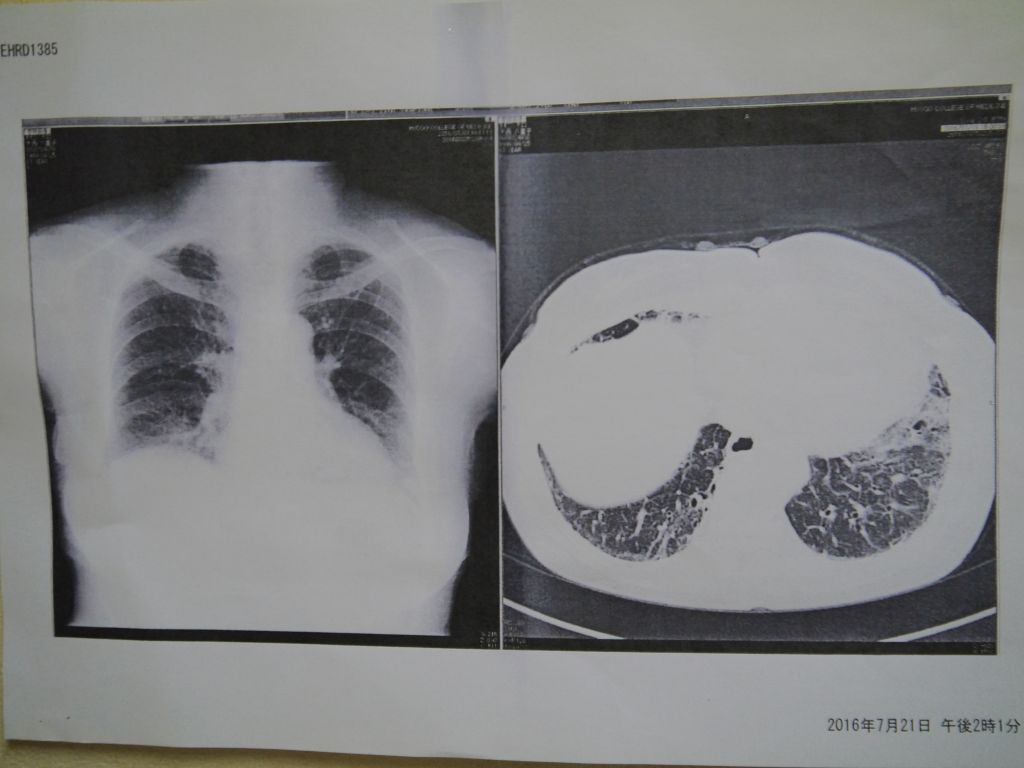

胸が重くて、息切れと咳は2ヶ月半位経っても良くならないから、平成28年2月15日に西宮市立中央病院に受診しました。血液検査したら、KL-6は2950に上がりました。担当医の先生からは、肺CTに白く映している部分はあります(サイズ未だ小さいです)、間質性肺炎です。有効なお薬がない病気で、徐々に進行し白く映る部分は大きくなると予測できますと聞きました。どうしても治りたいと思って、娘に頼んで色々調べて、貴院を見つけすぐ予約しました。貴院でお世話になってから間もなく2か月間続いた咳と胸の重苦しさは取れまして、呼吸も楽になりました。平成28年7月19日に兵庫医科大学で検査した所、KL-は380になり、間質性肺炎は治ったという結果になりました。貴院で一生治らいと言われた病気は5カ月位で治ったと思うとすごくうれしいです。(*下記の写真は、西様が西宮市立中央病院と兵庫医科大学で受けた検査結果の原本です)

左図は来院される前の病院での検査結果です。

2017年7月

左肺の上、両肺の下にすりガラス状の陰影像が見られ、病院では間質性肺炎と診断されました。

治療を開始して数カ月が経過し、病院にて検査を行いました。(左図参照)

CT検査では病気の進行を抑えることが出来ています。

2018年2月

病院の検査でCT画像を撮影したところ、以前まであった左肺のすりガラス状の陰影像は無くなり、両肺底の残存しているすりガラス状の陰影像でも軽快傾向で進行が抑えられているどころか、症状の改善が見られました。